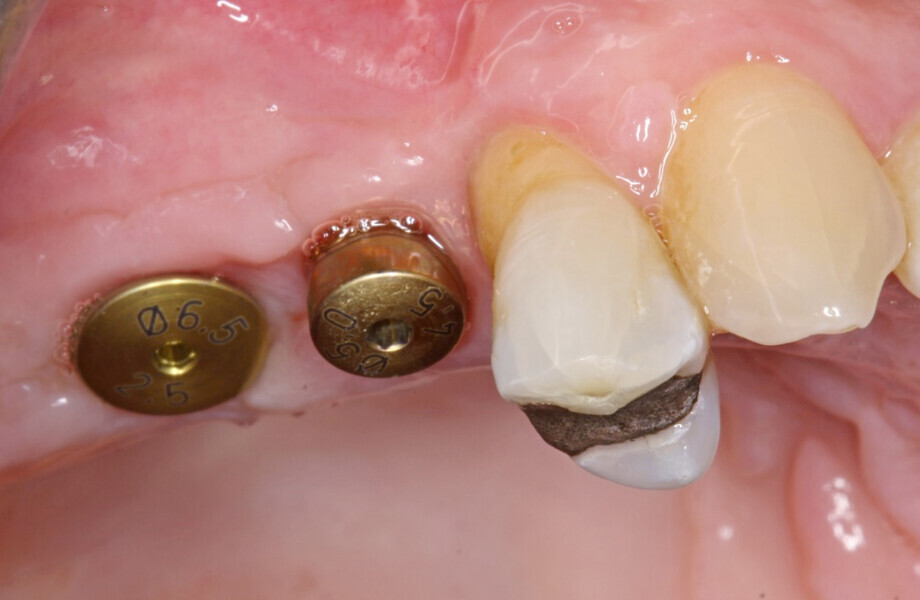

Next, the large quantity of autogenous bone collected with the disposable BoneTrap (Dentsply Sirona) during surgery was used to augment the small bone fenestration (Figs. 6 & 7), and Symbios Xenograft Granules were layered over the autogenous bone (Fig. 8). Finally, Symbios Collagen Membrane SR (15 × 20 mm) was trimmed to shape to complete the guided bone regeneration procedure (Fig. 9). The wound was closed with PGA sutures (Fig. 10), and radiographic evaluation was performed to verify the implants postoperatively (Fig. 11). Three months later, medium Healing Abutments EV were placed (Fig. 12).

Fig. 12: Healing Abutments EV placed at three months after initial surgery.